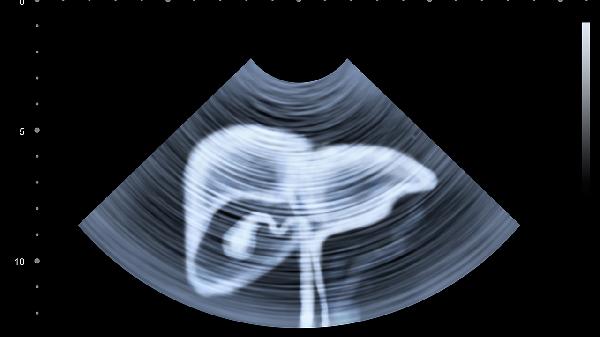

肝脏出现问题时,身体可能出现皮肤黄染、食欲减退、乏力、腹胀、尿液颜色加深等五种表现。这些症状可能与病毒性肝炎、脂肪肝、肝硬化、药物性肝损伤、胆道梗阻等疾病有关,建议及时就医检查肝功能、腹部超声等明确诊断。

出现上述症状应避免自行用药,特别是对乙酰氨基酚等具有肝毒性的药物。建议保持规律作息,控制体重在正常范围,接种乙肝疫苗预防感染。肝功能异常者需每3-6个月复查超声和甲胎蛋白,戒除烟酒等伤肝因素。烹饪选择蒸煮方式,减少烧烤腌制食品摄入,适量食用西蓝花、蓝莓等抗氧化食物。